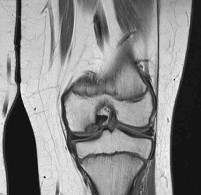

A 45-year-old recreational athlete presents with acute medial knee pain after feeling a 'pop' while deep squatting. MRI demonstrates an extrusion of the medial meniscus of 4 mm and a complete radial tear at the posterior root. Which of the following best describes the primary biomechanical consequence of this specific injury pattern?

A posterior medial meniscus root tear disrupts the circumferential hoop stresses that the intact meniscus relies on to dissipate axial loads. Biomechanical studies demonstrate that a posterior root tear is functionally equivalent to a total meniscectomy in terms of decreasing contact area and dramatically increasing peak tibiofemoral contact pressures, leading to rapid chondrolysis and osteoarthritis if left untreated.